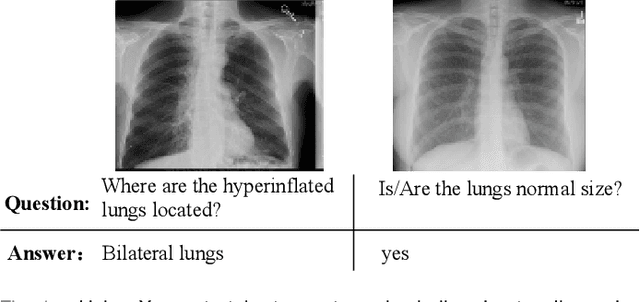

Abstract:Medical Visual Question Answering (VQA) is a multi-modal challenging task widely considered by research communities of the computer vision and natural language processing. Since most current medical VQA models focus on visual content, ignoring the importance of text, this paper proposes a multi-view attention-based model(MuVAM) for medical visual question answering which integrates the high-level semantics of medical images on the basis of text description. Firstly, different methods are utilized to extract the features of the image and the question for the two modalities of vision and text. Secondly, this paper proposes a multi-view attention mechanism that include Image-to-Question (I2Q) attention and Word-to-Text (W2T) attention. Multi-view attention can correlate the question with image and word in order to better analyze the question and get an accurate answer. Thirdly, a composite loss is presented to predict the answer accurately after multi-modal feature fusion and improve the similarity between visual and textual cross-modal features. It consists of classification loss and image-question complementary (IQC) loss. Finally, for data errors and missing labels in the VQA-RAD dataset, we collaborate with medical experts to correct and complete this dataset and then construct an enhanced dataset, VQA-RADPh. The experiments on these two datasets show that the effectiveness of MuVAM surpasses the state-of-the-art method.